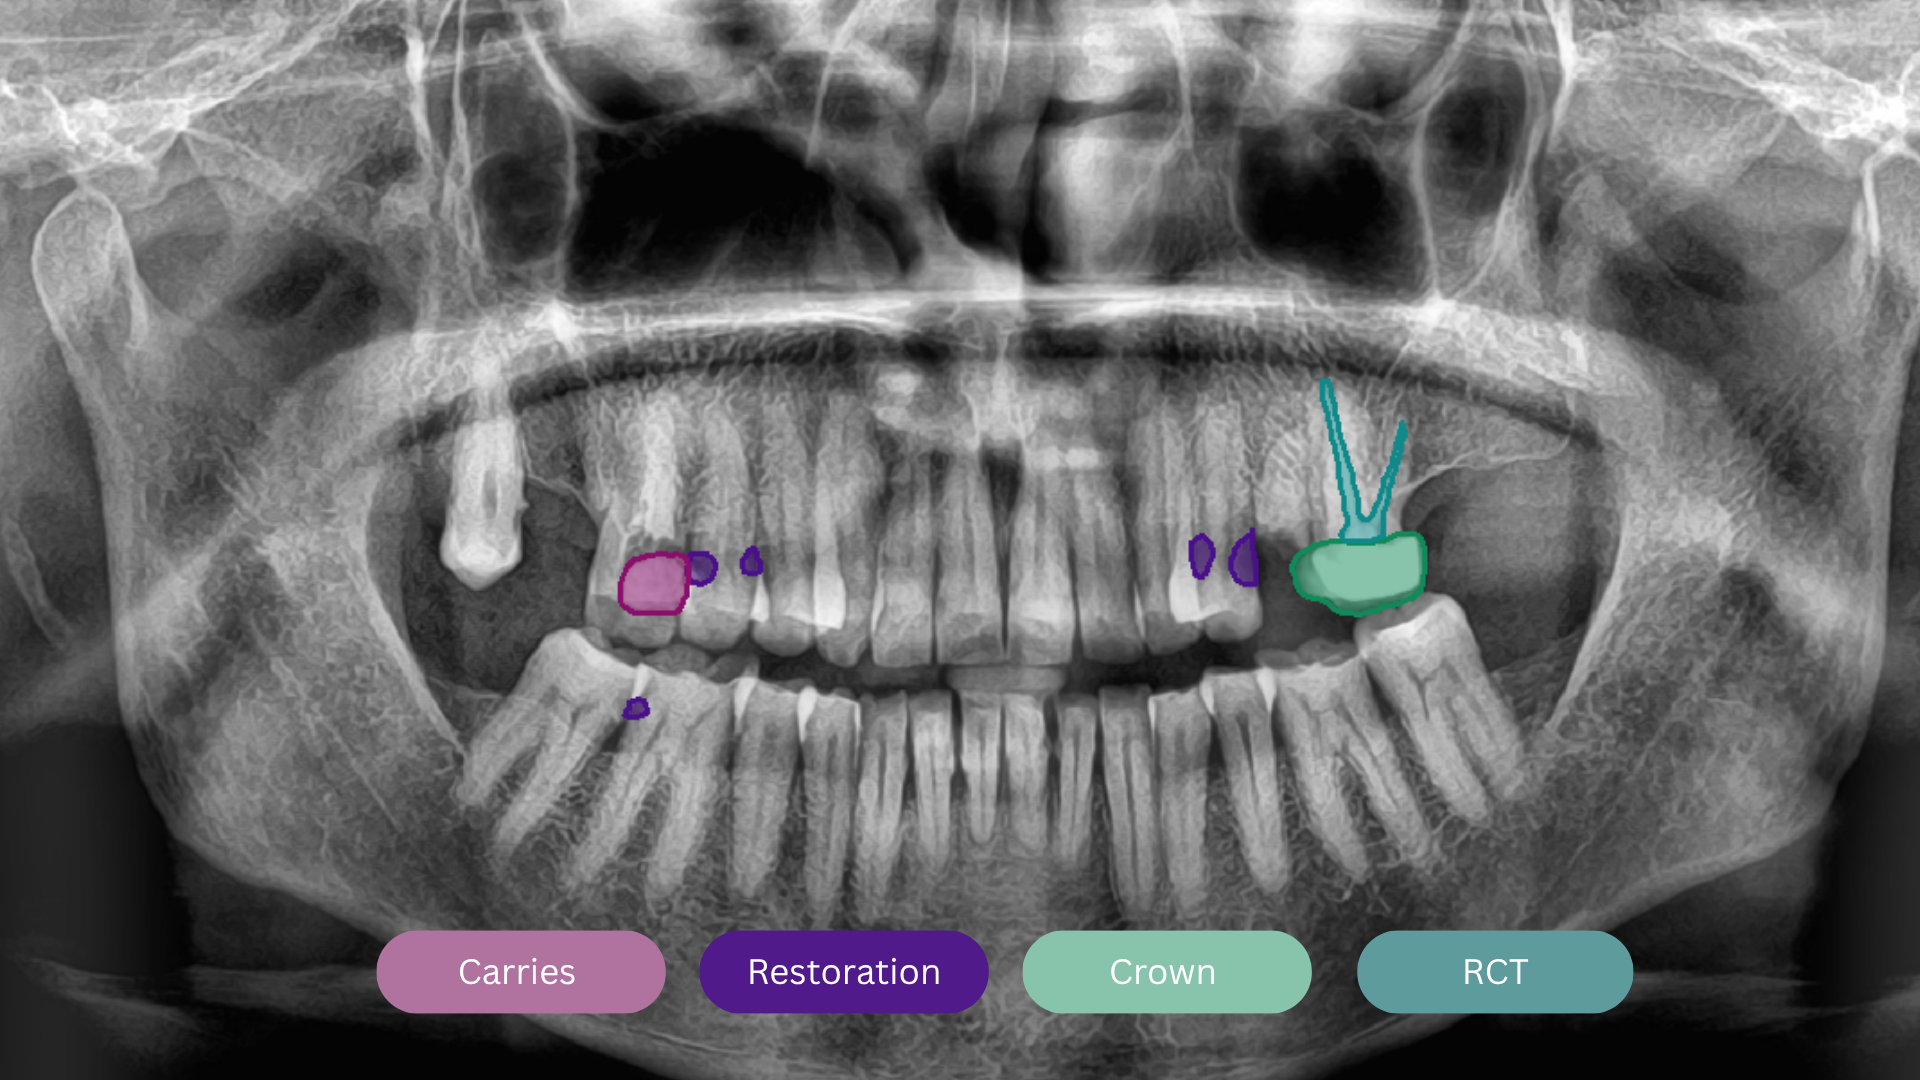

X-ray Analyzer

Our AI delivers instant, high-accuracy X-ray analysis for faster diagnoses and confident treatment decisions. Fully integrates into your clinic for smarter care.

- Advanced AI dental software with an AI dental assistant for X-ray analysis

AI-Driven Diagnosis

Make confident diagnoses with intelligent AI X-ray analysis.